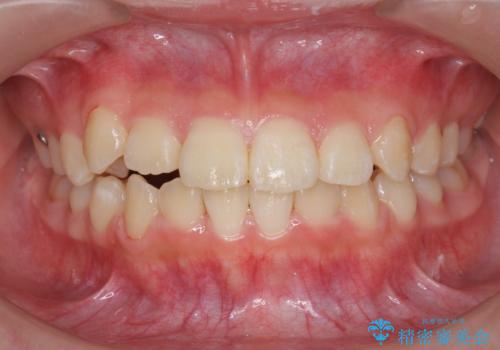

インビザラインで行う八重歯の治療

- 笑った時に目立つ八重歯の矯正治療を求めて来院されました。

マイクロインプラントを用いた臼歯の後方牽引、およびゴムかけ等の付加処置を駆使して八重歯の治療を行っていきます。